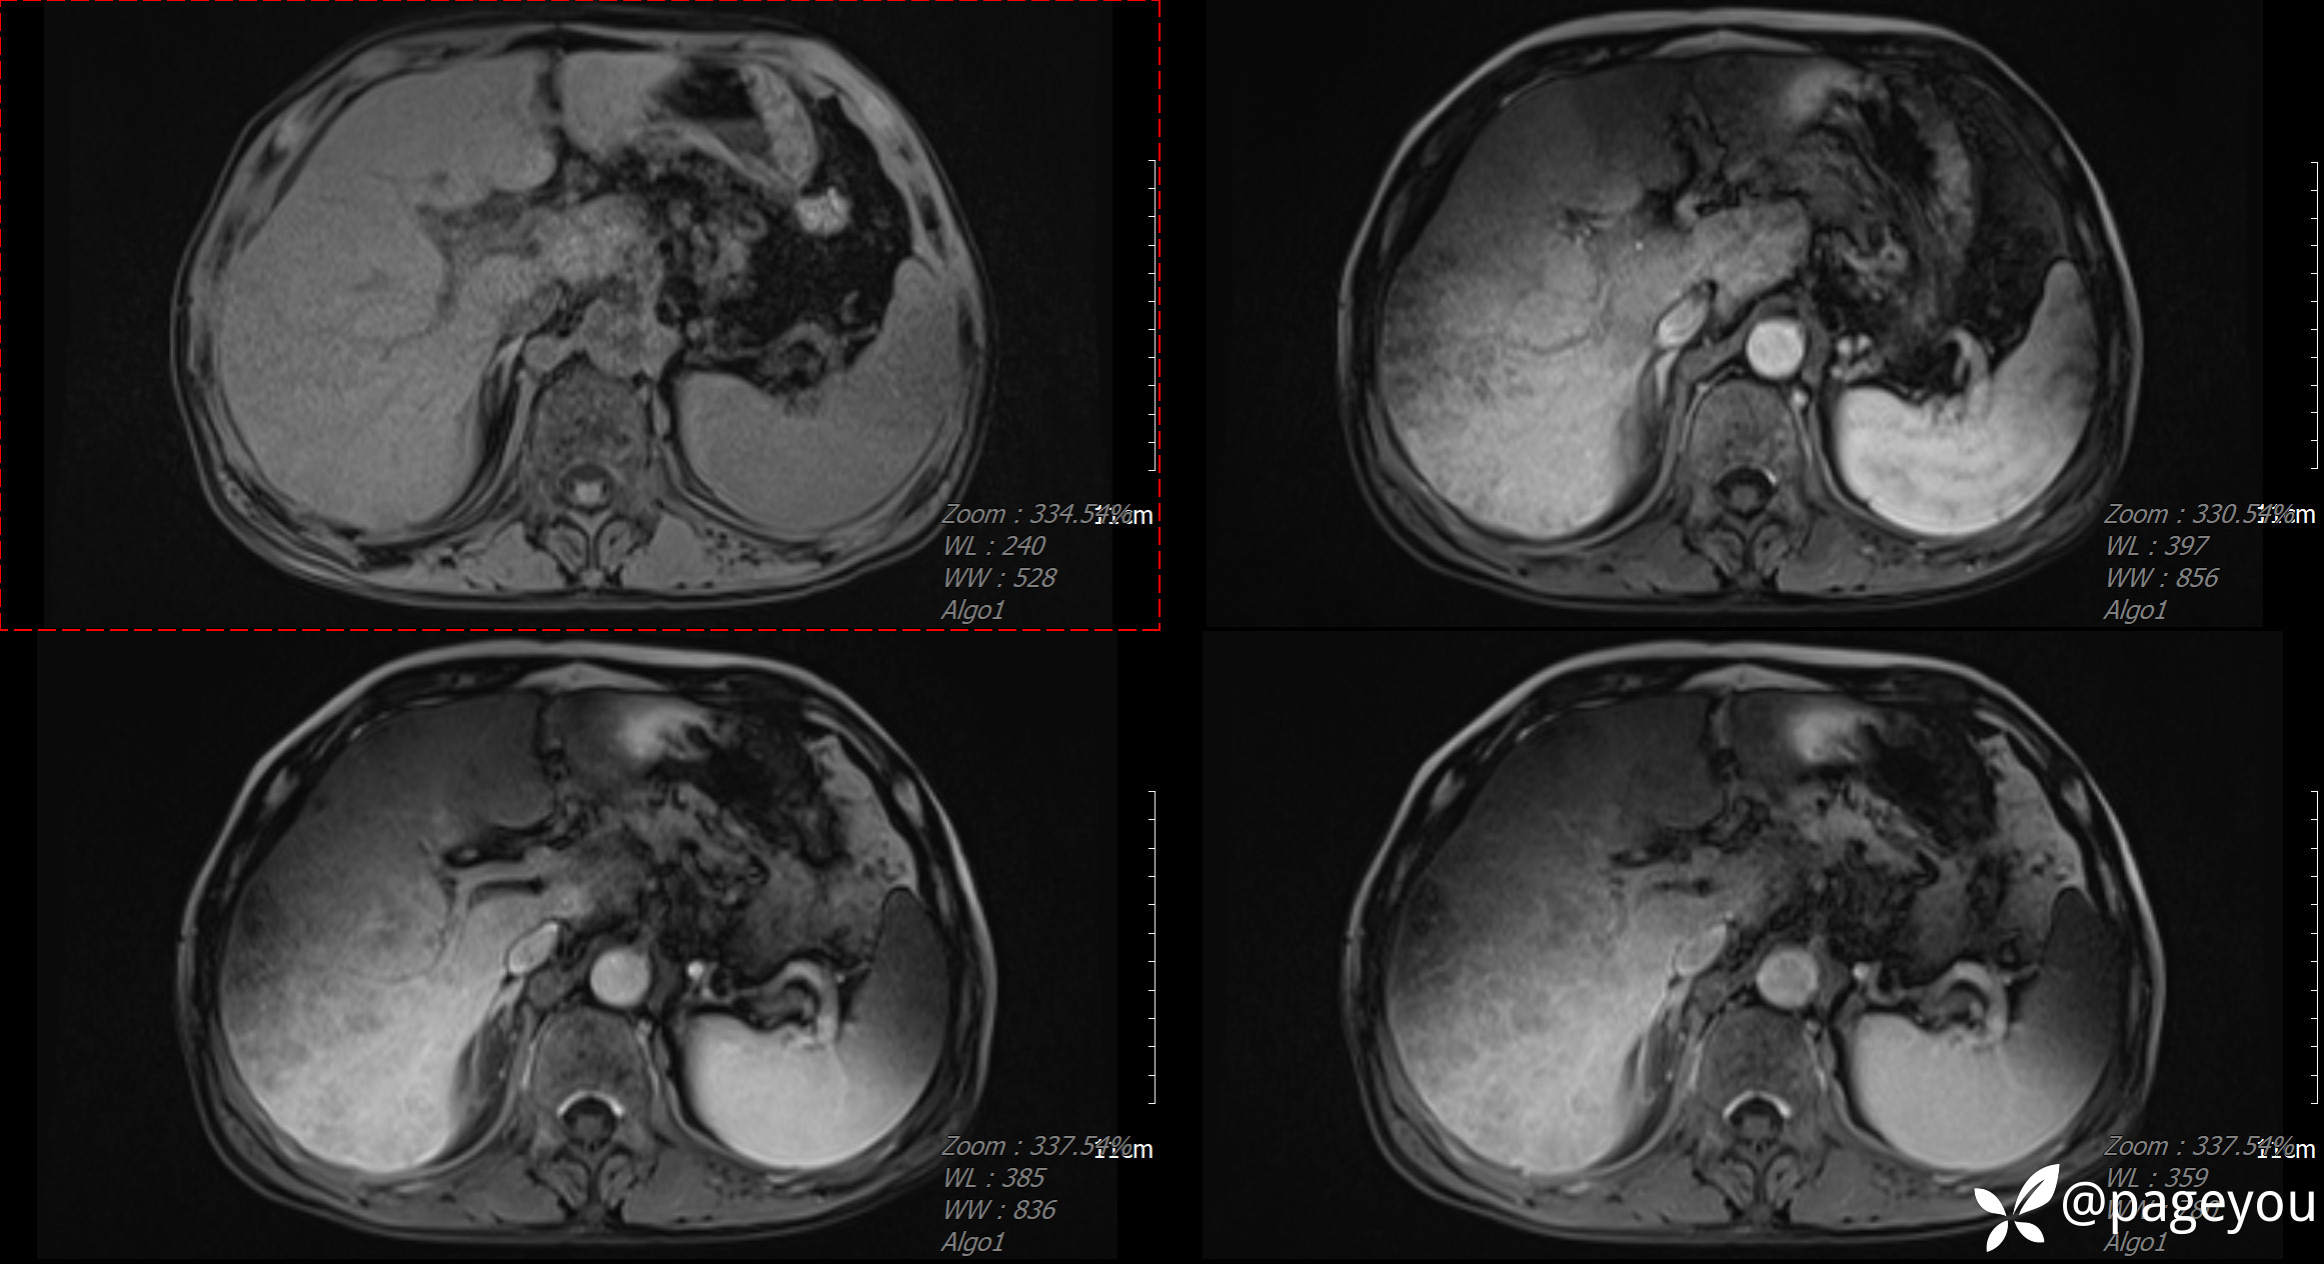

CT检查:

MRI检查: